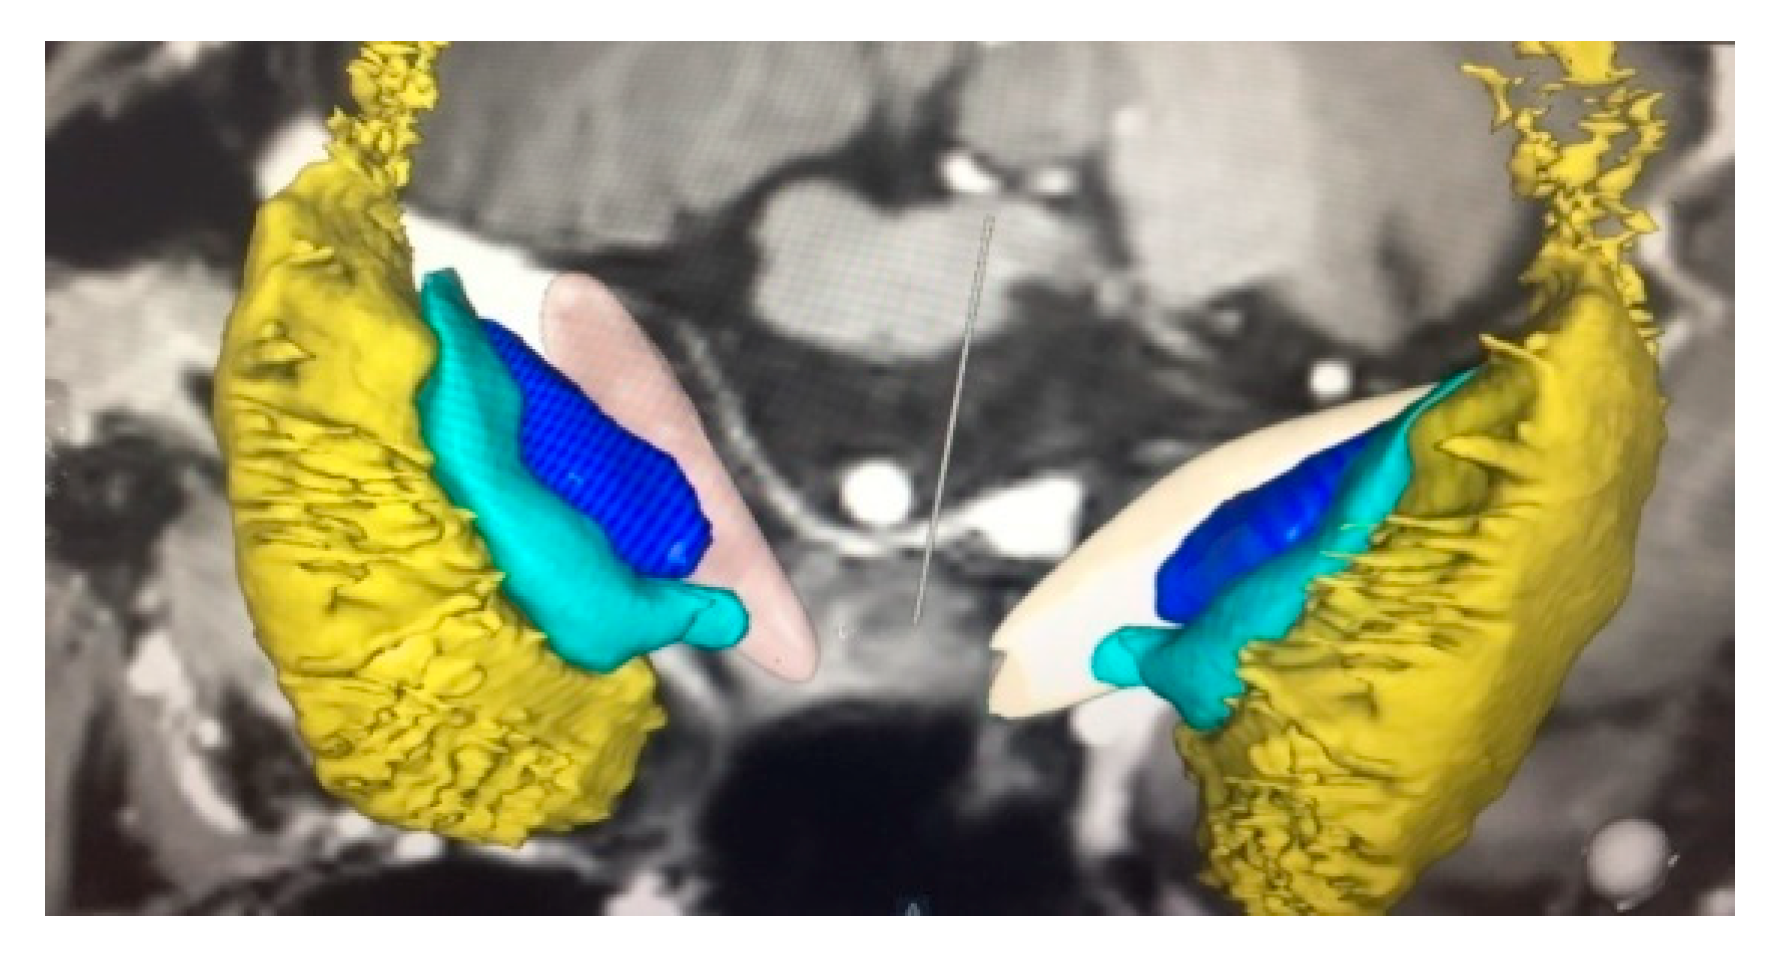

2.4. Operative Technique